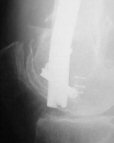

A. Difficult reductions, even in retrograde nailing (my preference, easier control of "small" distal fragment) and it is much, much harder to do it anterograde (Alex, do you have one good case in your collection of anterograde nailing in very distal fractures - as you have suggested that I

should have done it in my previously posted case?

Malpositioning is much too common (recurvatum, varus - valgus).

B. Fixation loosening: distal cutting of the nail, non-unions do happen (cases attached).